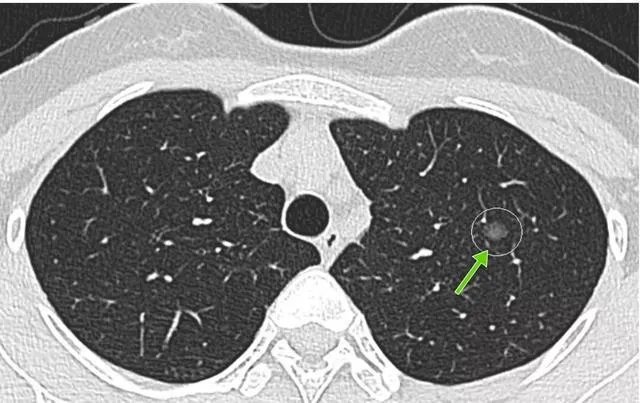

在了解肺结节之前,先给大家科普一下肺结节的定义,在医学上,我们一般将在肺部X光片或者CT检查中,直径小于3cm的高于正常肺组织的异常密度影,称之为肺结节,它的形态一般呈圆形或者类圆形,密度可以是稍高于肺组织,也可以明显高于肺组织。

根据大小的差异,又可以分小结节、微小结节等;小结节的直径一般小于10mm,在4—10mm之间,而微小结节的直径一般就是小于4mm的。

而对于小于10mm的小结节,就需要结合数量、形态以及有无危险因素进行综合判断,如果无法确定性质,那么最重要的就是随访复查。也就是间隔一段时间后再次进行胸部CT检查,通过观察对比前后两次检查,判断结节是否有大小的变化、密度的变化、形态的变化、数量的变化等等。

对于良性的结节,它在随访的过程中,一般不会出现明显的变化,有的甚至会消失;而对于恶性的结节,那么在随访的过程中则可能出现密度增高、体积增大等等。